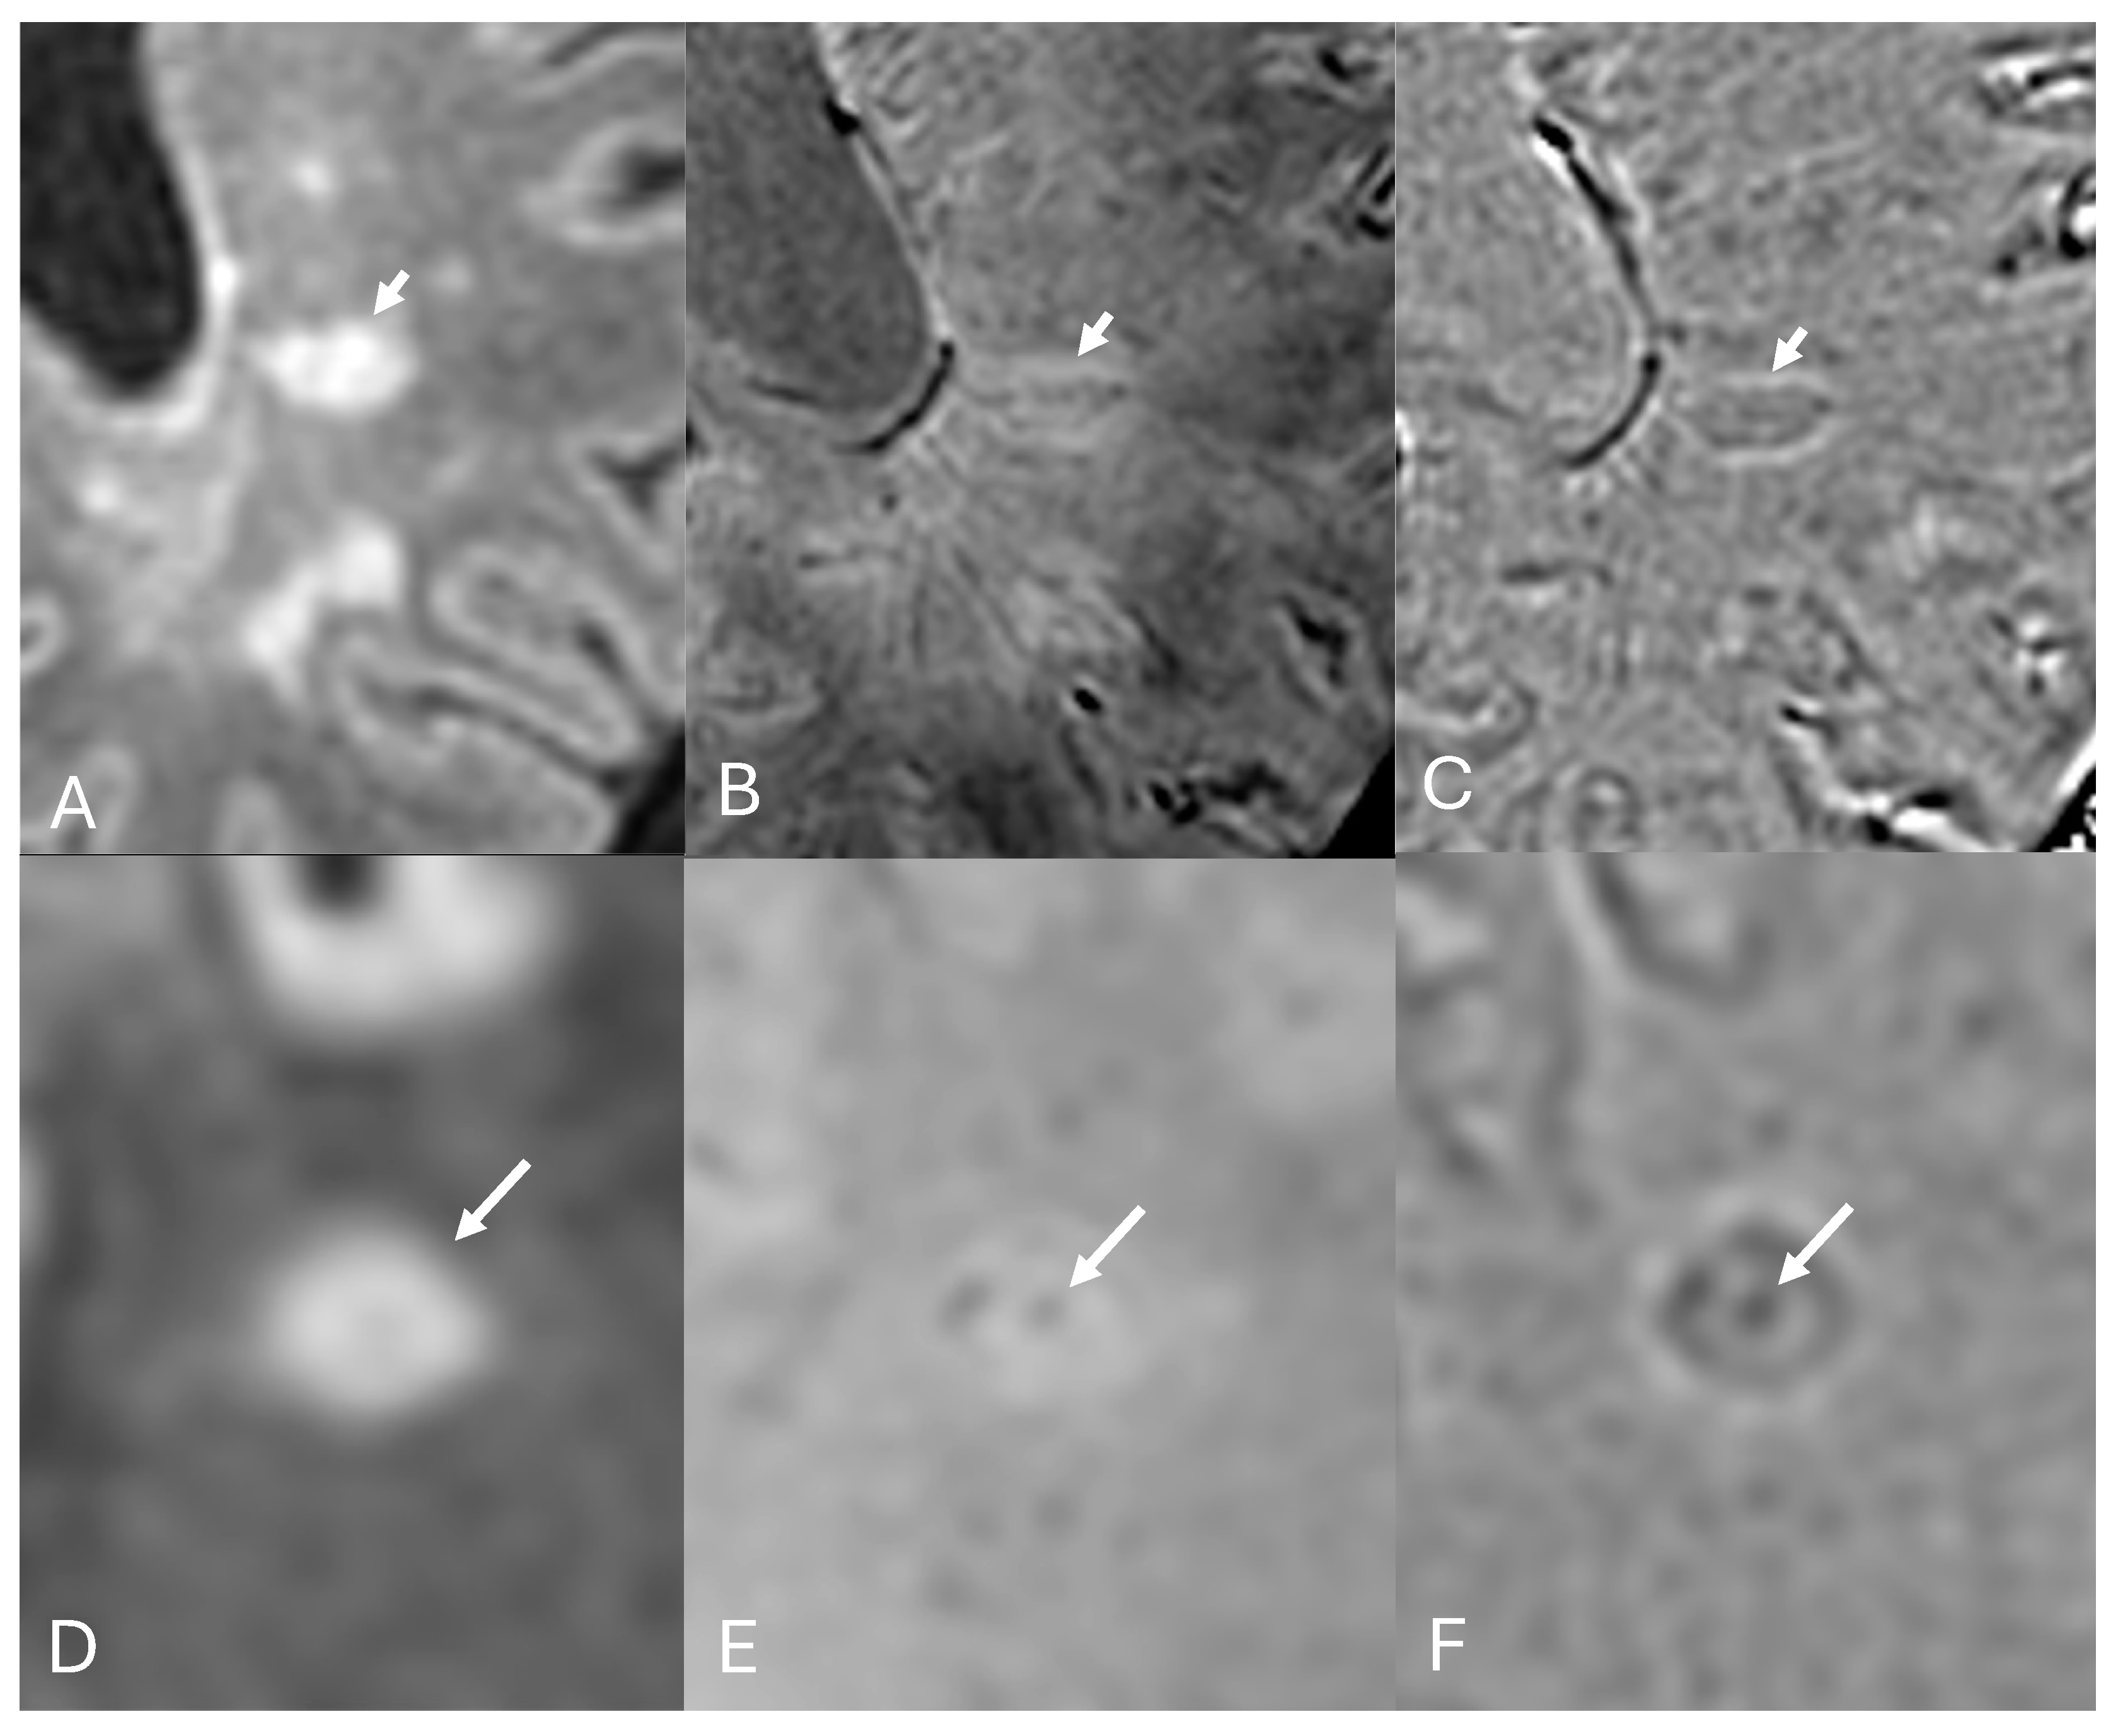

3.1. Central Vein Sign